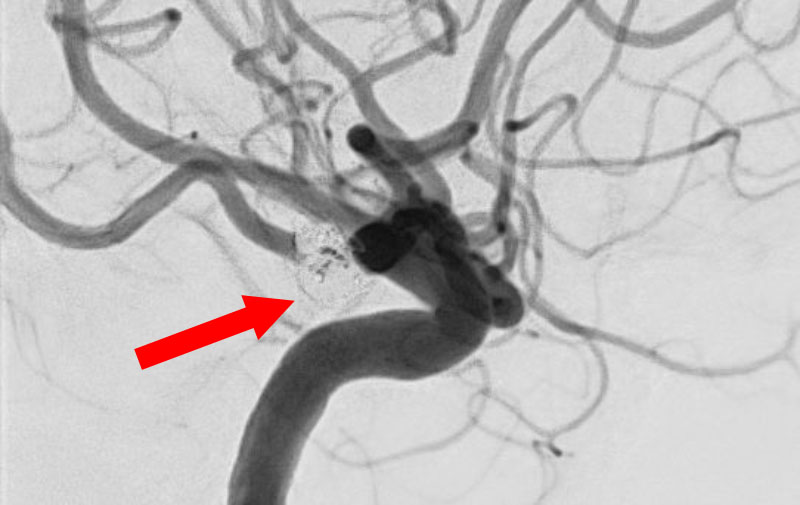

No.1630 手術前

No.1630 手術中

No.1630 手術後